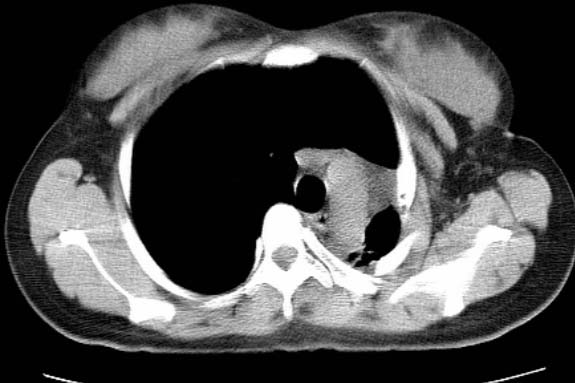

标题: CT25648:求教:是肺发育不全还是结核?

女  20岁。一月前咳血,诊“肺结核”抗痨治疗一月后,咳血停止,现复查。病人精神好。前后ct片对比未见明显变化。既往体检“正常”

1)考虑左肺结核并肺不张、支气管扩张。2)纵隔疝。

考虑左肺结核,左肺毁损,纵膈左偏,既往体检正常不可靠,tb一个月也不会这个样子的,有钙化,应该病程较长,冰冻三尺非一日之寒!

左肺发育不全。